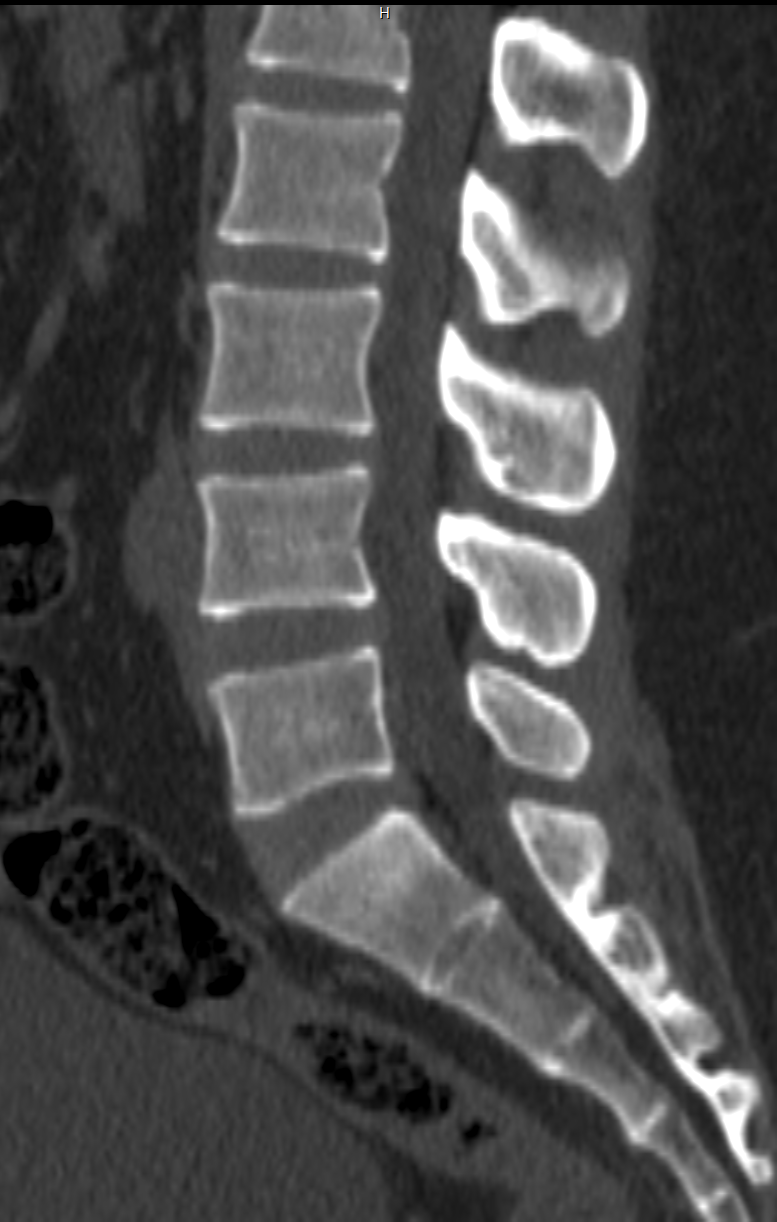

Musculoskeletal System | Fractures, complex joint injuries, osteomyelitis | Ligament/tendon tears, meniscal injuries, cartilage damage, bone marrow edema |

Spine | Spinal fractures, spinal instability, bone lesions | Spinal cord tumors, disc herniation, nerve root compression, inflammatory conditions |